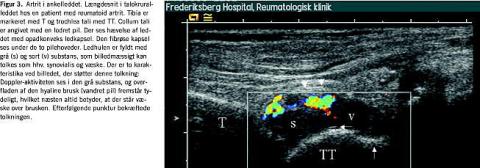

Hos patienter med kliniske tegn på inflammation kunne farve-Doppler anvendes på de overfladenære led og seneskeder. Der kunne således påvises Doppler-aktivitet i alle de små led på hænder og fødder (Figur 1 ), i sternoklavikulærled, albueled, ankelled og knæled. I modsætning hertil var Doppler-aktivitet kun undtagelsesvist til stede i dybereliggende led som f.eks. skulderled og hofteled trods klinisk erkendelig ledsygdom, typisk artrit. Hos raske kontrolpersoner kunne der påvises Doppler-aktivitet i visse led. Således var det et næsten konstant fund ved undersøgelse af leddet mellem caput radii og capitulum humeri, mens det sjældnere blev observeret i håndled og ikke i fingerled. Der kunne ligeledes påvises Doppler-aktivitet både i og omkring symptomgivende akillessener og ligamenta patellae. Seneskeder med klinisk tenosynovit med og uden gråtone-UL-forandringer havde overvejende Doppler-aktivitet langs senen (Figur 2 ). Doppler-funktionen kunne ligeledes supplere gråtonebilledet ved differentiering af en meget ekkofattig synovialis fra fri væske i led og omkring sener ved påvisning af kar i den ekkofatt ige del af vævet (Figur 3 ).

Tolkningen af synovialishypertrofi kan være vanskelig på gråtoneultralyd, hvor der enten kan være tale om aktuel, igangværende sygdom eller spor af et tidligere, nu udslukt angreb. Farve-Doppler kan her give differentialdiagnostisk hjælp, idet farvede pixler (hyperæmi) tyder på igangværende inflammation. Fundet af kar ved farve-Doppler er dog ikke ensbetydende med inflammation. Dette understreges af påvisningen af kar i normale led med anvendelsen af meget følsomt apparatur. Forholdene omkring placeringen af normale kar i de enkelte led er dog relativt konstante, og trænede undersøgere vil derfor kunne skelne hyperæmi fra de sædvanlige kar ved lokalisationen alene.